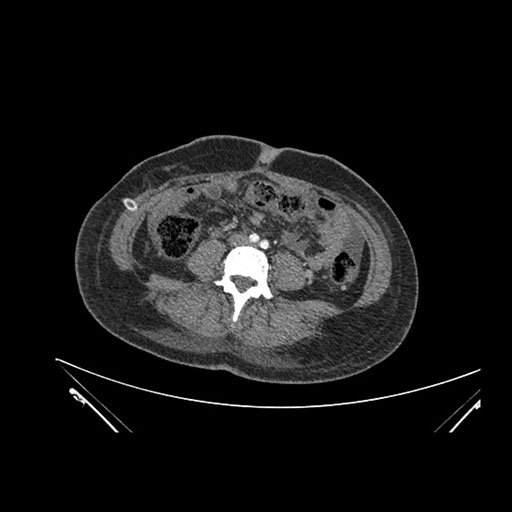

Axial Arterial

Axial Venous